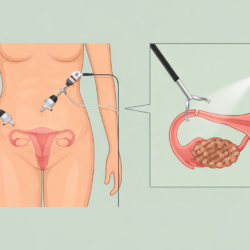

Die Hysterektomie wird heutzutage meist laparoskopisch durchgeführt. Dank dieser Methode wird die Gebärmutter über kleine Schnitte entfernt, ohne dass ein großer Schnitt im Bauchbereich erforderlich ist. Die laparoskopische Chirurgie bietet der Patientin Vorteile wie weniger Schmerzen, eine kürzere Krankenhausaufenthaltsdauer und eine schnellere Genesung.

Im Cyprus American IVF Center werden Hysterektomie-Eingriffe mit fortschrittlichen chirurgischen Techniken und einem erfahrenen Spezialistenteam sicher durchgeführt. Unter Berücksichtigung des allgemeinen Gesundheitszustands, der Beschwerden und der Erwartungen der Patientin wird der am besten geeignete Behandlungsplan erstellt.